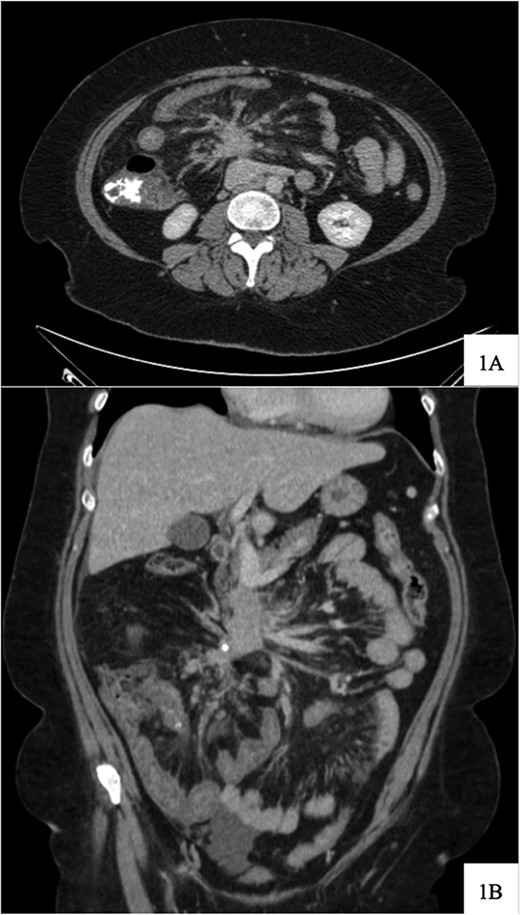

Regarding her oncologic history, she was diagnosed with NET in October of 2017 when a computed tomography (CT) scan performed for intermittent abdominal cramping and diarrhea revealed a mass near the third portion of the duodenum and the root of the mesentery (Fig. 1). Biopsy of the mass revealed a well-differentiated NET. Further work-up with DOTATATE positron emission tomography (PET)/CT revealed a small bowel primary likely emanating from the terminal ileum as well as multiple lesions in the neck, chest, and liver (Figs 2 and 3). The periduodenal mass intimately involved the root of the mesentery, SMA, and SMV. She was initially treated with Lanreotide for many years with close monitoring and later underwent systemic treatment with Lutathera, a Peptide Receptor Radionuclide Therapy, from April 2020 to November 2020. She subsequently resumed Lanreotide in December of 2020, which she was on at the time of admission. Her disease remained largely stable on imaging over the next three years; however, her symptoms had been worsening over the few months leading up to her presentation.

DOTATATE positron emission tomography-computed tomography scan revealing extent of metastatic disease.